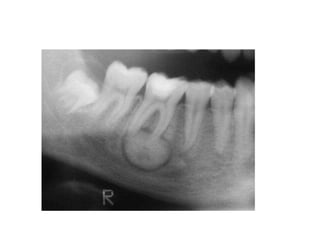

• Most often a well-corticated multilocular

radiolucency.

• “Honey-comb”, “soap-bubble” or “tennis-racket”

appearance.

• May be a well-corticated unilocular lesion

Honeycomb-like small

ameloblastoma at early stage with

evidence of root resorption.